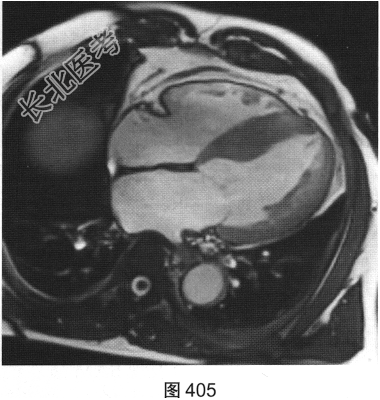

- [材料题] 患者男性,43岁,因“活动后胸痛3年”,外地医院拟诊梗阻性肥厚型心肌病,为明确诊断而转诊本院。

- 简答题3、患者超声心动图检查未能明确诊断,临床申请心脏磁共振检查,如图404~图408所示。患者心脏磁共振检查的异常征象有?